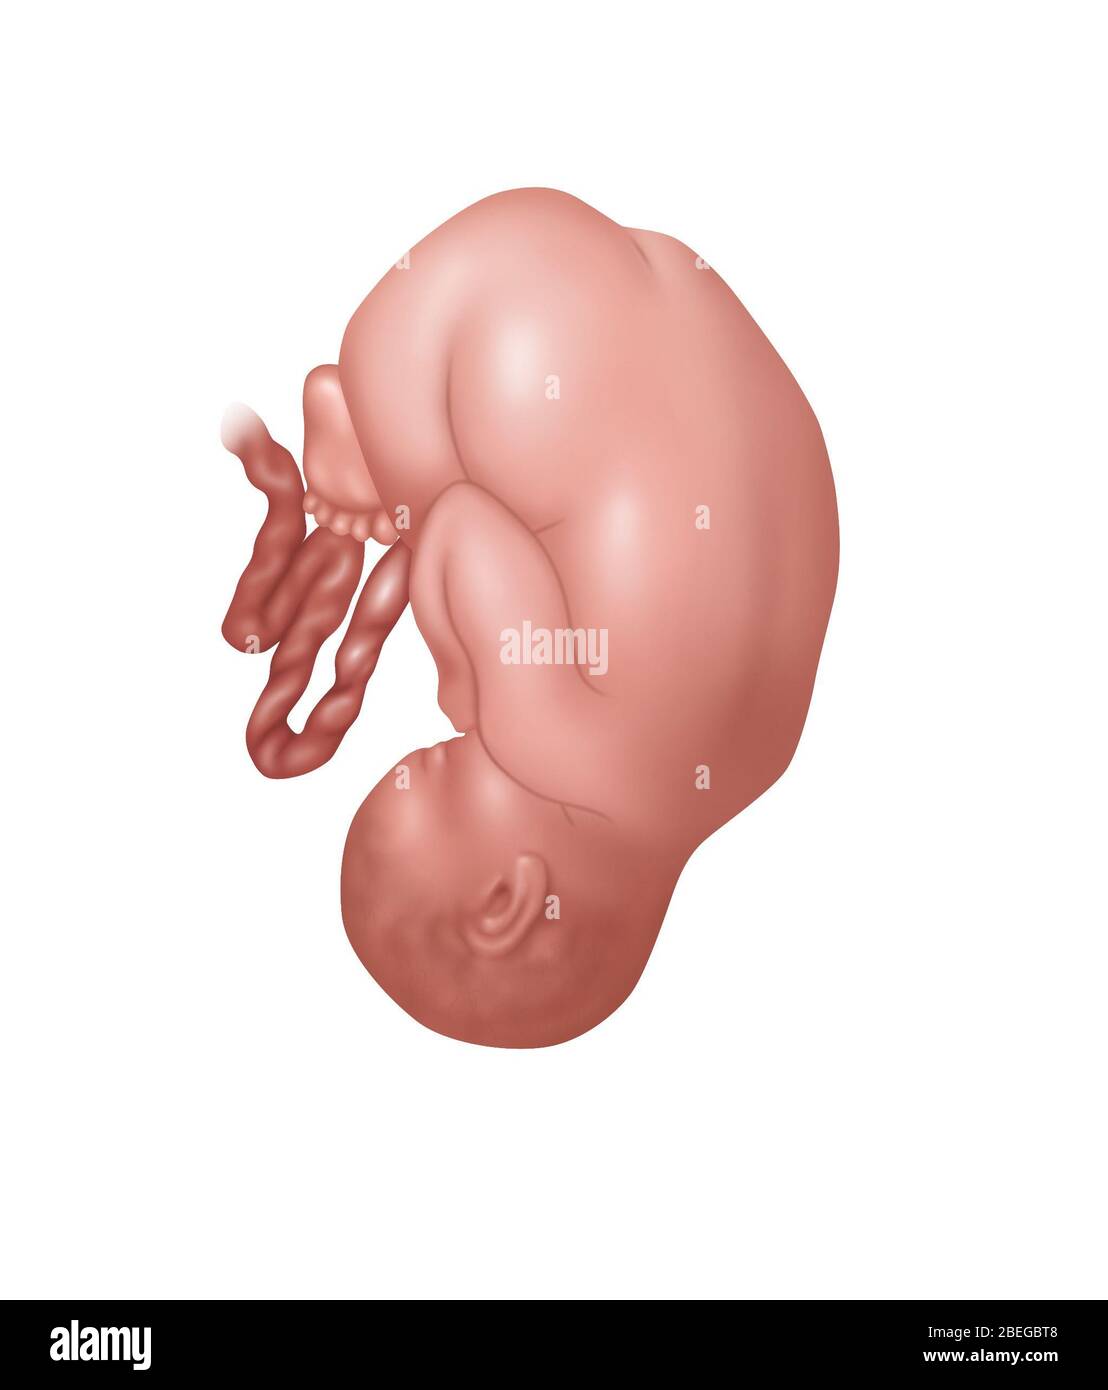

Fetus Positions in Uterus, Illustration Stock Photohttps://www.alamy.com/image-license-details/?v=1https://www.alamy.com/fetus-positions-in-uterus-illustration-image353173031.html

Fetus Positions in Uterus, Illustration Stock Photohttps://www.alamy.com/image-license-details/?v=1https://www.alamy.com/fetus-positions-in-uterus-illustration-image353173031.htmlRF2BEGBPF–Fetus Positions in Uterus, Illustration

Fetus Positions in Uterus, Illustration Stock Photohttps://www.alamy.com/image-license-details/?v=1https://www.alamy.com/fetus-positions-in-uterus-illustration-image353173074.html

Fetus Positions in Uterus, Illustration Stock Photohttps://www.alamy.com/image-license-details/?v=1https://www.alamy.com/fetus-positions-in-uterus-illustration-image353173074.htmlRF2BEGBT2–Fetus Positions in Uterus, Illustration